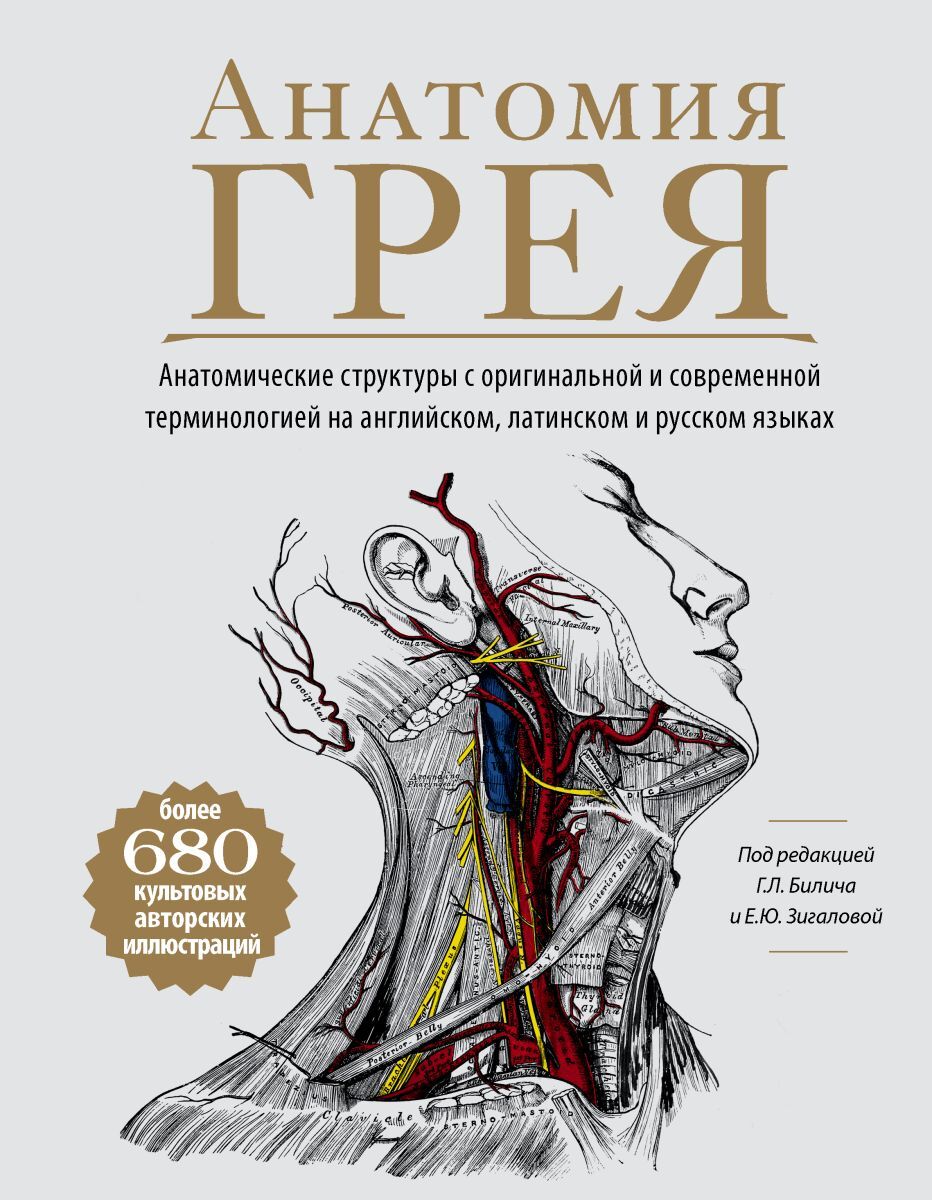

Написанная в 1850-х годах молодым врачом Генри Греем, "Анатомия Грея" была самой всеобъемлющей и доступной анатомией своего времени. Книга, которую вы держите в руках, содержит исторический текст второго издания и все авторские рисунки Генри Вандайка Карт

Написанная в 1850-х годах молодым врачом Генри Греем, "Анатомия Грея" была самой всеобъемлющей и доступной анатомией своего времени. Книга, которую вы держите в руках, содержит исторический текст второго издания и все авторские рисунки Генри Вандайка Карт